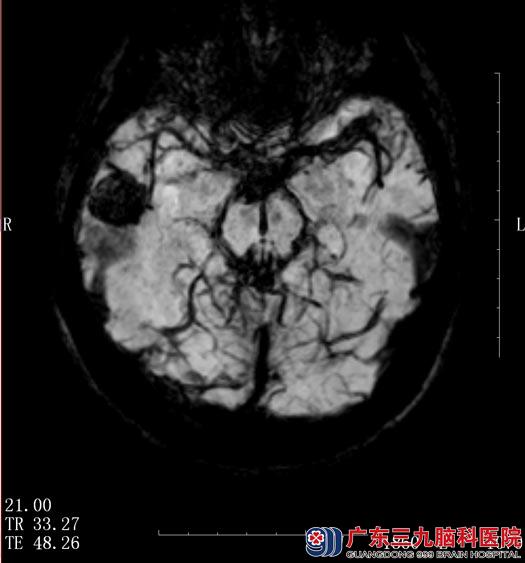

当地医院行头颅CT检查,考虑为右侧颞叶病变。入住广东三九脑科医院综合神经外科,头颅MR检查示“右颞叶占位,直径约2cm,考虑海绵状血管瘤”,动态脑电图示“右颞叶重度异常脑电反应”。

鲁明主任阅片后考虑右侧颞叶海绵状血管瘤,根据脑电图显示,陈女士的癫痫发作与海绵状血管瘤关系密切。

▲手术前